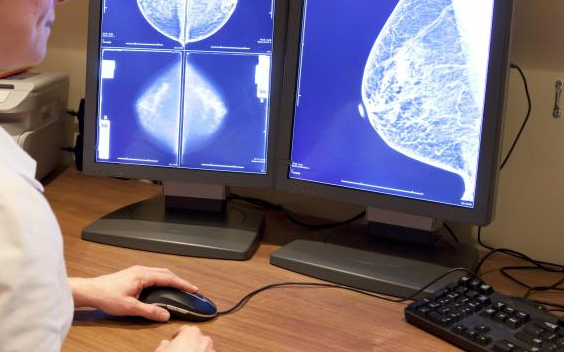

Először Magyarországon vált elérhetővé a régióban a jóindulatú emlődaganat műtét nélküli eltávolítása

A régióban elsőként Magyarországon elérhetővé vált a jóindulatú emlődaganatok egyik leggyakoribb típusának műtét nélküli eltávolítása fagyasztásos eljárással, krioablációval

- közölte az eljárást végző egészségközpont az MTI-vel. Deák Pál Ákos, a Semmelweis Egyetem és a Premier Med Egészségközpont intervenciós radiológusa, valamint Forrai Gábor radiológus, az Európai Emlődiagnosztikai Társaság elnöke a közleményben jelentős előrelépésnek nevezte a fagyasztásos eljárás megjelenését, amellyel a jóindulatú emlődaganatok közül a fibroadenomák eltávolításakor elkerülhető a műtét és az ezzel járó szövődmények, pszichés terhek is.

A módszerrel nagyon alacsony hőmérsékleten, célzottan pusztítják el a kóros elváltozást, nem érintve az egészséges szöveteket. A fagyasztást követően a daganatok mintegy fél év alatt felszívódnak - közölték.

Az eljárást az Egyesült Államokban és Nyugat-Európában több mint tíz éve hatékonyan alkalmazzák a prosztata, máj, vese és egyéb szervek jóindulatú és rákos daganatainak kezelésére - írták. Forrai Gábor megerősítette, hogy a jövőben a rosszindulatú daganatok kezelésénél is szóba jöhet az eljárás.

Magyarországon az eljárást a társadalombiztosítás egyelőre nem finanszírozza. A százmillió forintos beruházás révén végzett beavatkozás kiterjesztését a tapasztalatok függvényében hosszú távon megfontolják egyéb daganatos megbetegedések kezelésére is. A Németországban már rutinszerűen használt eljárás számos daganattípus esetén alkalmazható, ezért vélhetően a kezelési repertoár Magyarországon is bővülni fog - írták.

A közlemény szerint a magyar nők 15 százaléka küzd melltumorral, a probléma főként az 50 év alattiakat érinti. A fibroadenoma nem okoz áttétet, nem veszélyezteti a beteg életét, viszont növekedhet és eldeformálhatja az emlőket.